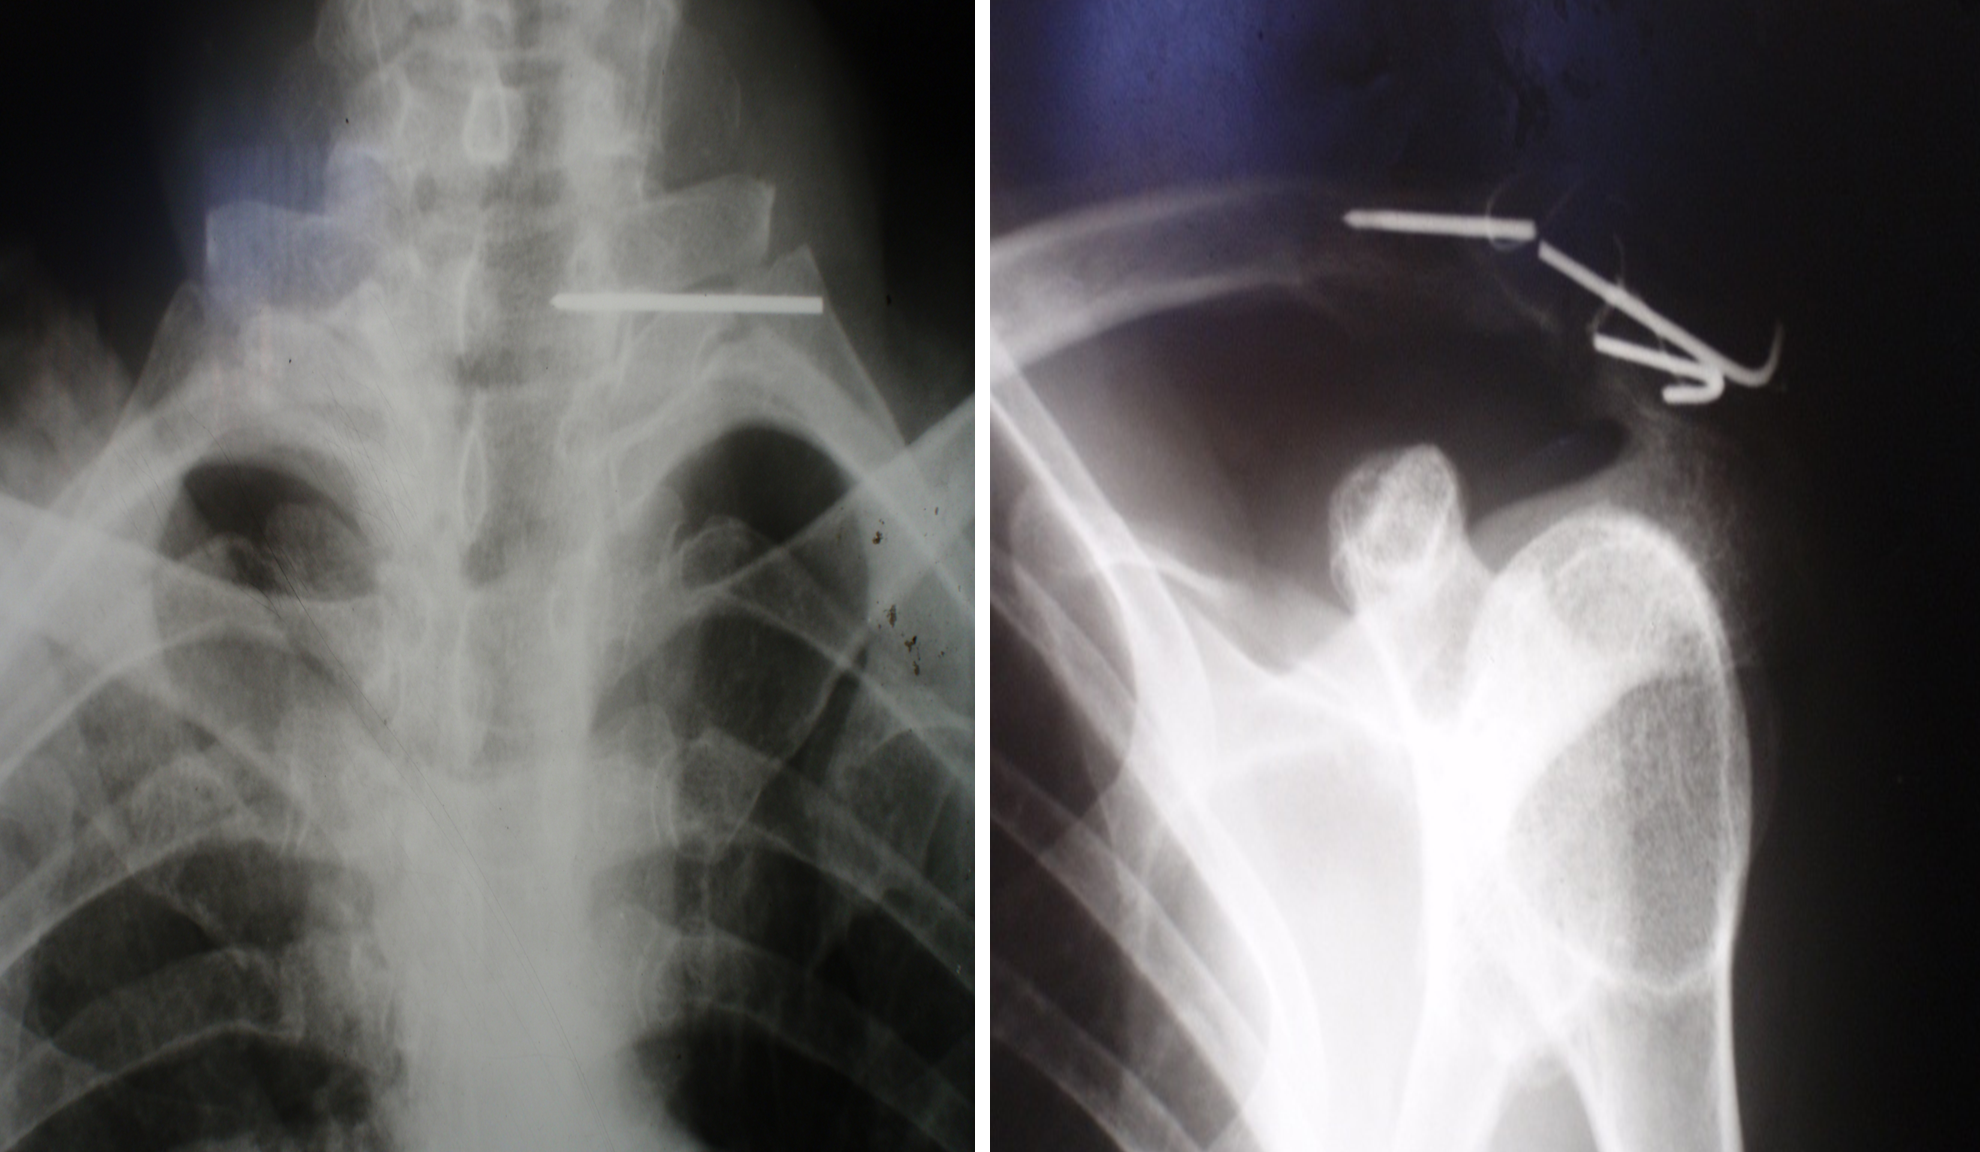

The correctness of our assumptions was confirmed when, after some time, a 40-year-old patient C came to the clinic with complaints of pain in the cervical spine. In 2007, he underwent osteosynthesis of the acromioclavicular joint with two crossed Kirschner wires, which were also not removed. An X-ray examination revealed a fracture of the wires, migration of one of the fragments, and its insertion into the cervical spine (Fig. 4). The patient underwent surgery, and the foreign bodies were removed.

Figure 4. X-ray images of the left shoulder joint and the cervical spine of patient C. Fracture of the pins and migration of one of the proximal fragments.